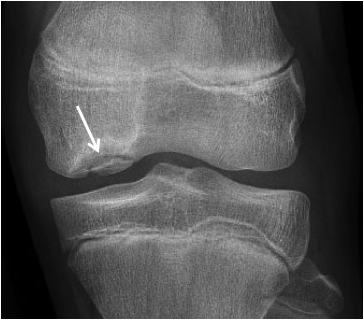

Обычный рентгеновский снимок — лучшее начальное исследование, которое может помочь в диагностике